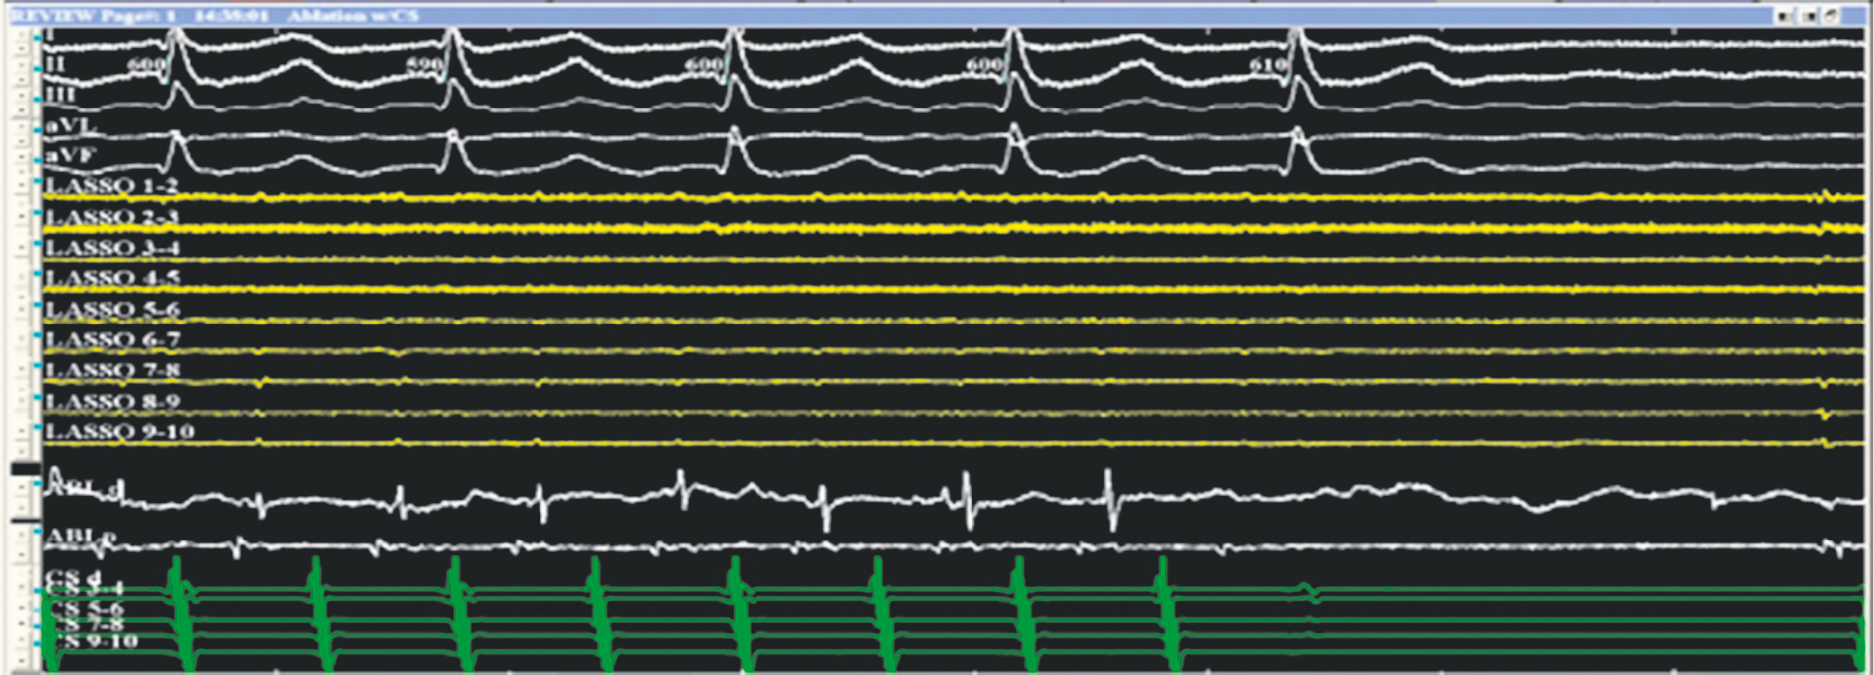

Fig. 5. Fragment of the operation of radiofrequency ablation of septal atrial flutter after the labyrinth-3 operation, arrest of arrhythmia and restoration of sinus rhythm during ablation. Top–down: standard electrocardiogram leads, signals from a multipole circular electrode (yellow) on the left atrial posterior wall, signals from an ablation electrode (white), and signals from a multipole electrode in the coronary sinus (green). The EPT system “Claris” (Abbott, USA) was used. The recording speed was 200 mm/s

Рис. 5. Фрагмент операции радиочастотной аблации септального трепетания предсердий после операции лабиринт-3, купирование аритмии и восстановление синусового ритма во время аблации. Сверху вниз: стандартные отведения ЭКГ, сигналы с многополюсного циркулярного электрода (желтые) на задней стенке левого предсердия, сигналы с аблационного электрода (белые), сигналы с многополюсного электрода в коронарном синусе (зеленые). ЭФИ система «Claris» (Abbot, США). Скорость записи 200 мм/с